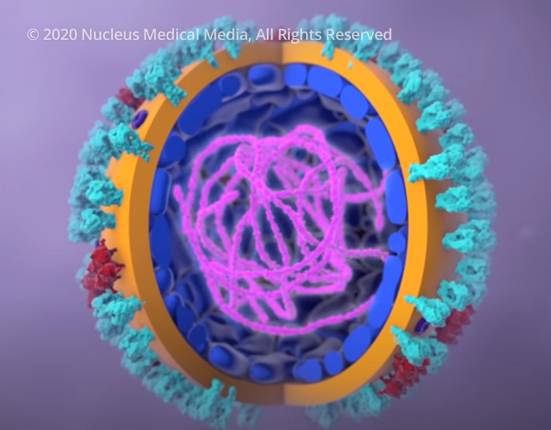

为了更加直观的看它的结构,我们把它放大并给它的各个部分上个颜色。

可以看到在灰色的蛋白质外壳上均匀镶嵌着大量的冠状突起,这种独特的长相就是它叫冠状病毒的原因。

进一步我们剖开它的内部,一团紫色的线状物质映入眼帘,这是它所有的遗传物质 RNA,也是病毒赖以生存和繁殖的根本。

总的来说,病毒由一堆蛋白质组件和其内部的 RNA 构成。